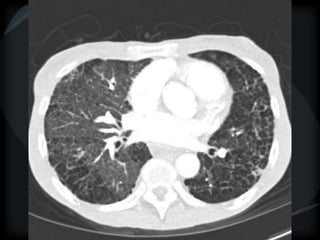

RETICULAR PATTERN - UIP

 peripheral reticular lines / inter and intralobular septae

 honeycomb

 Traction bronchiectasis

 None or minimal ground glass

 Gradient increasing from apex to base

 Skip areas

 Diagnostic accuracy high

 Idiopathic

 Familial

 CVD - RA

 Drugs – NFT, Busulphan

 Asbestosis = basilar – bands – pleural calcification

 Chronic HP = upper and midzones

 Hermansky-Pudlak syndrome

Acute exacerbation of UIP

● above + ground glass

● Peripheral – better prognosis – Fibroblastic Foci+++

● Diffuse – worse prognosis – DAD

AMJRCCM.198:372;2008

AIP

● Diffuse ground glass + airspace

● Traction bronchiectasis

● honeycomb

UIP

Chronic HP

Asbestosis